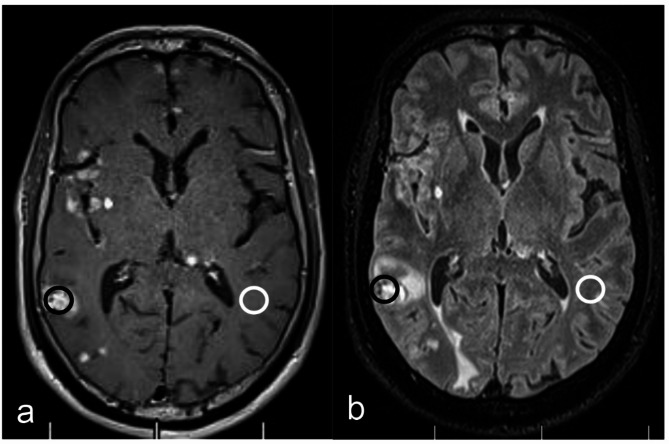

Objective: To investigate the diagnostic value of CE-MATRIX-T1FLAIR and 3D CE-T2FLAIR sequences based on Contrast Enhancement Modulated flip Angle Technique in Refocused Imaging with eXtended echo train (CE-MATRIX) technology for detecting Leptomeningeal Metastasis (LM) using Fluid Attenuated Inversion Recovery (FLAIR) imaging.

Methods: This prospective study included 563 hospitalized patients with clinically suspected LM, diagnosed with malignant tumors between January 2022 and October 2023 at Henan Cancer Hospital. Both CE-MATRIX-T1FLAIR and 3D CE-T2FLAIR sequences were used for imaging. Two radiologists independently evaluated image quality, diagnostic confidence, and objective measurements, diagnosing LM as positive or negative, with disagreements resolved by consultation. Subjective and objective scores were compared using the Wilcoxon signed-rank test. The diagnostic performance of the sequences was compared using ROC curve analysis, with cerebrospinal fluid (CSF) cytology as the gold standard. Sensitivity, specificity, positive predictive value (PPV), negative predictive value (NPV), accuracy, and area under the curve (AUC) values were calculated and compared using Z-tests.

Results: LM was confirmed in 321 patients. CE-MATRIX-T1FLAIR showed superior subjective scores in image quality and diagnostic confidence (p < 0.001). Though CE-MATRIX-T1FLAIR had a lower SNR (p = 0.013), it demonstrated higher sensitivity, specificity, PPV, NPV, accuracy, and AUC than 3D CE-T2FLAIR (p < 0.001). Both sequences provided effective diagnosis and differentiation of LM.

Conclusion: CE-MATRIX-T1FLAIR offers superior diagnostic performance compared to 3D CE-T2FLAIR for LM, with slightly better subjective ratings despite a lower SNR. Both sequences are effective for diagnosing LM.